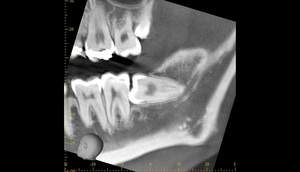

3ヶ月のCT画像①

麻布十番歯科での1回目の親知らず抜歯から3ヶ月後のCT画像①

3ヶ月のCT画像②

麻布十番歯科での1回目の親知らず抜歯から3ヶ月後のCT画像②

1回目から3ヶ月待ちました。下歯槽神経の位置が根の先から離れているのが確認できます。

これで下歯槽神経を損傷させることなく、親知らずの抜歯を行うことができます。